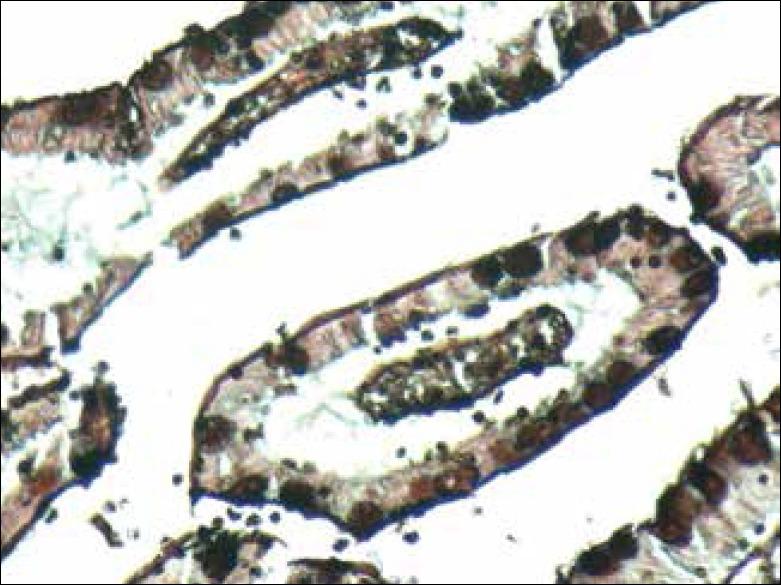

Enteric protozoan infections are a well-documented cause of diarrhea in immunocompromised patients. Special stains on stool specimens are routinely performed in such patients to diagnose these protozoa namely cryptosporidium, microsporidium, and isospora. Duodenal and jejunal biopsies can also be performed to obtain a tissue diagnosis. We report a case of microsporidium enteritis diagnosed on histopathological examination of small bowel resection specimen in a case of perforation peritonitis. The patient was a known HIV-positive on antiretroviral treatment for 2 years and on antitubercular treatment for 3 months. This case report highlights the importance of carefully screening the resection specimens for protozoal infections in immunocompromised individuals. The association of perforation peritonitis and microsporidium is rare. Hence, the possibility that untreated microsporidium infection can lead to perforation cannot be ruled out.